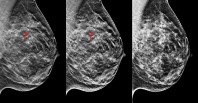

მკერდის თვითპროფილაქტიკა

ჯანმრთელი და ლამაზი მკერდის შესანარჩუნებლად, ქალი ვალდებულია, მონიტორინგი აწარმოოს. პირველ რიგში, უნდა იცოდეთ, ნებისმიერი პათოლოგიის გამოვლენაში თვითგასინჯვა დაგეხმარებათ.